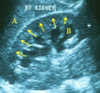

What can be seen at points:

A?

B?

Arrows?

A) Right lobe of liver

B) Dilated calyx

C) Renal cortex